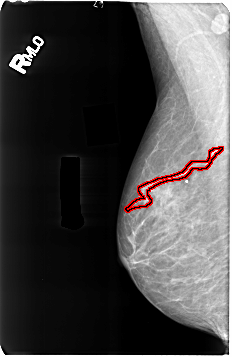

B_3164_1.RIGHT_MLO

FILE: B_3164_1.RIGHT_MLO.OVERLAY

TOTAL_ABNORMALITIES 1

ABNORMALITY 1

LESION_TYPE CALCIFICATION TYPE VASCULAR DISTRIBUTION N/A

ASSESSMENT 2

SUBTLETY 4

PATHOLOGY BENIGN_WITHOUT_CALLBACK

TOTAL_OUTLINES 1

BOUNDARY